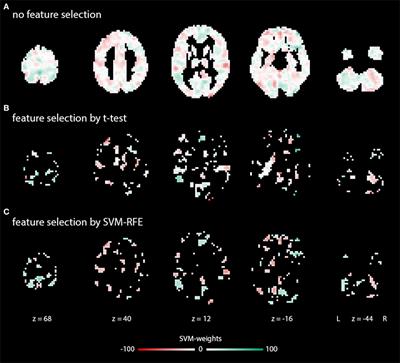

Cognitive-Behavioral Therapy for Obsessive–Compulsive Disorder with and without Autism Spectrum Disorder: Gray Matter Differences Associated with Poor Outcome